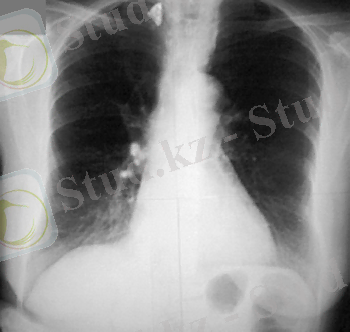

Біріншілік туберкулезді кешен- біріншілік туберкулездің ошақты формасы. Оның спецификалық зақымдануының 3 компоненті бар: перифокальді реакциямен жүретін біріншілік аффект, регионарлы лимфа түйіндерінің туберкулезі және оларды байланыстыратын лимфангит туберкулезі аймағы (8. 5. және8. 6 -шы суреттер )

Біріншілік туберкулезді кешеннің кері дамуы өкпедегі перифокальді инфильтрацияның баяу сіңірілуімен, казеозды массалардың тығыздалып, кальций тұздарын сіңірумен сипатталады. Қалыптасқан ошақ айналасында гиалин капсуласы пайда болады. Біртіндеп өкпелік компоненттің орнына Гон ошағы түзіледі де, уақыт өте сүйектенеді. (8. 7. сурет) Зақымдалған лимфа түйіндерінде репаративті процесстер өкпелік ошаққа қарағанда біршама баяу жүреді. Оларда кальцинат түзілуімен аяқталады. Лимфангиттің жазылуы перибронхиальды және периваскулиярлы тіндердің фиброзды тығыздалуымен жүреді.

Өкпедегі Гон ошағы мен лимфа түйіндерінде кальцинаттың түзілуі біріншілік туберкулезді кешеннің клиникалық жазылуының морфологиялық дәлелі болып табылады да, орташа і біріншілік туберкулезді кешеннің клиникалық жазылуының морфологиялық дәлелі болып табылады да, орташа 3, 5- 5 жылда дамиды.